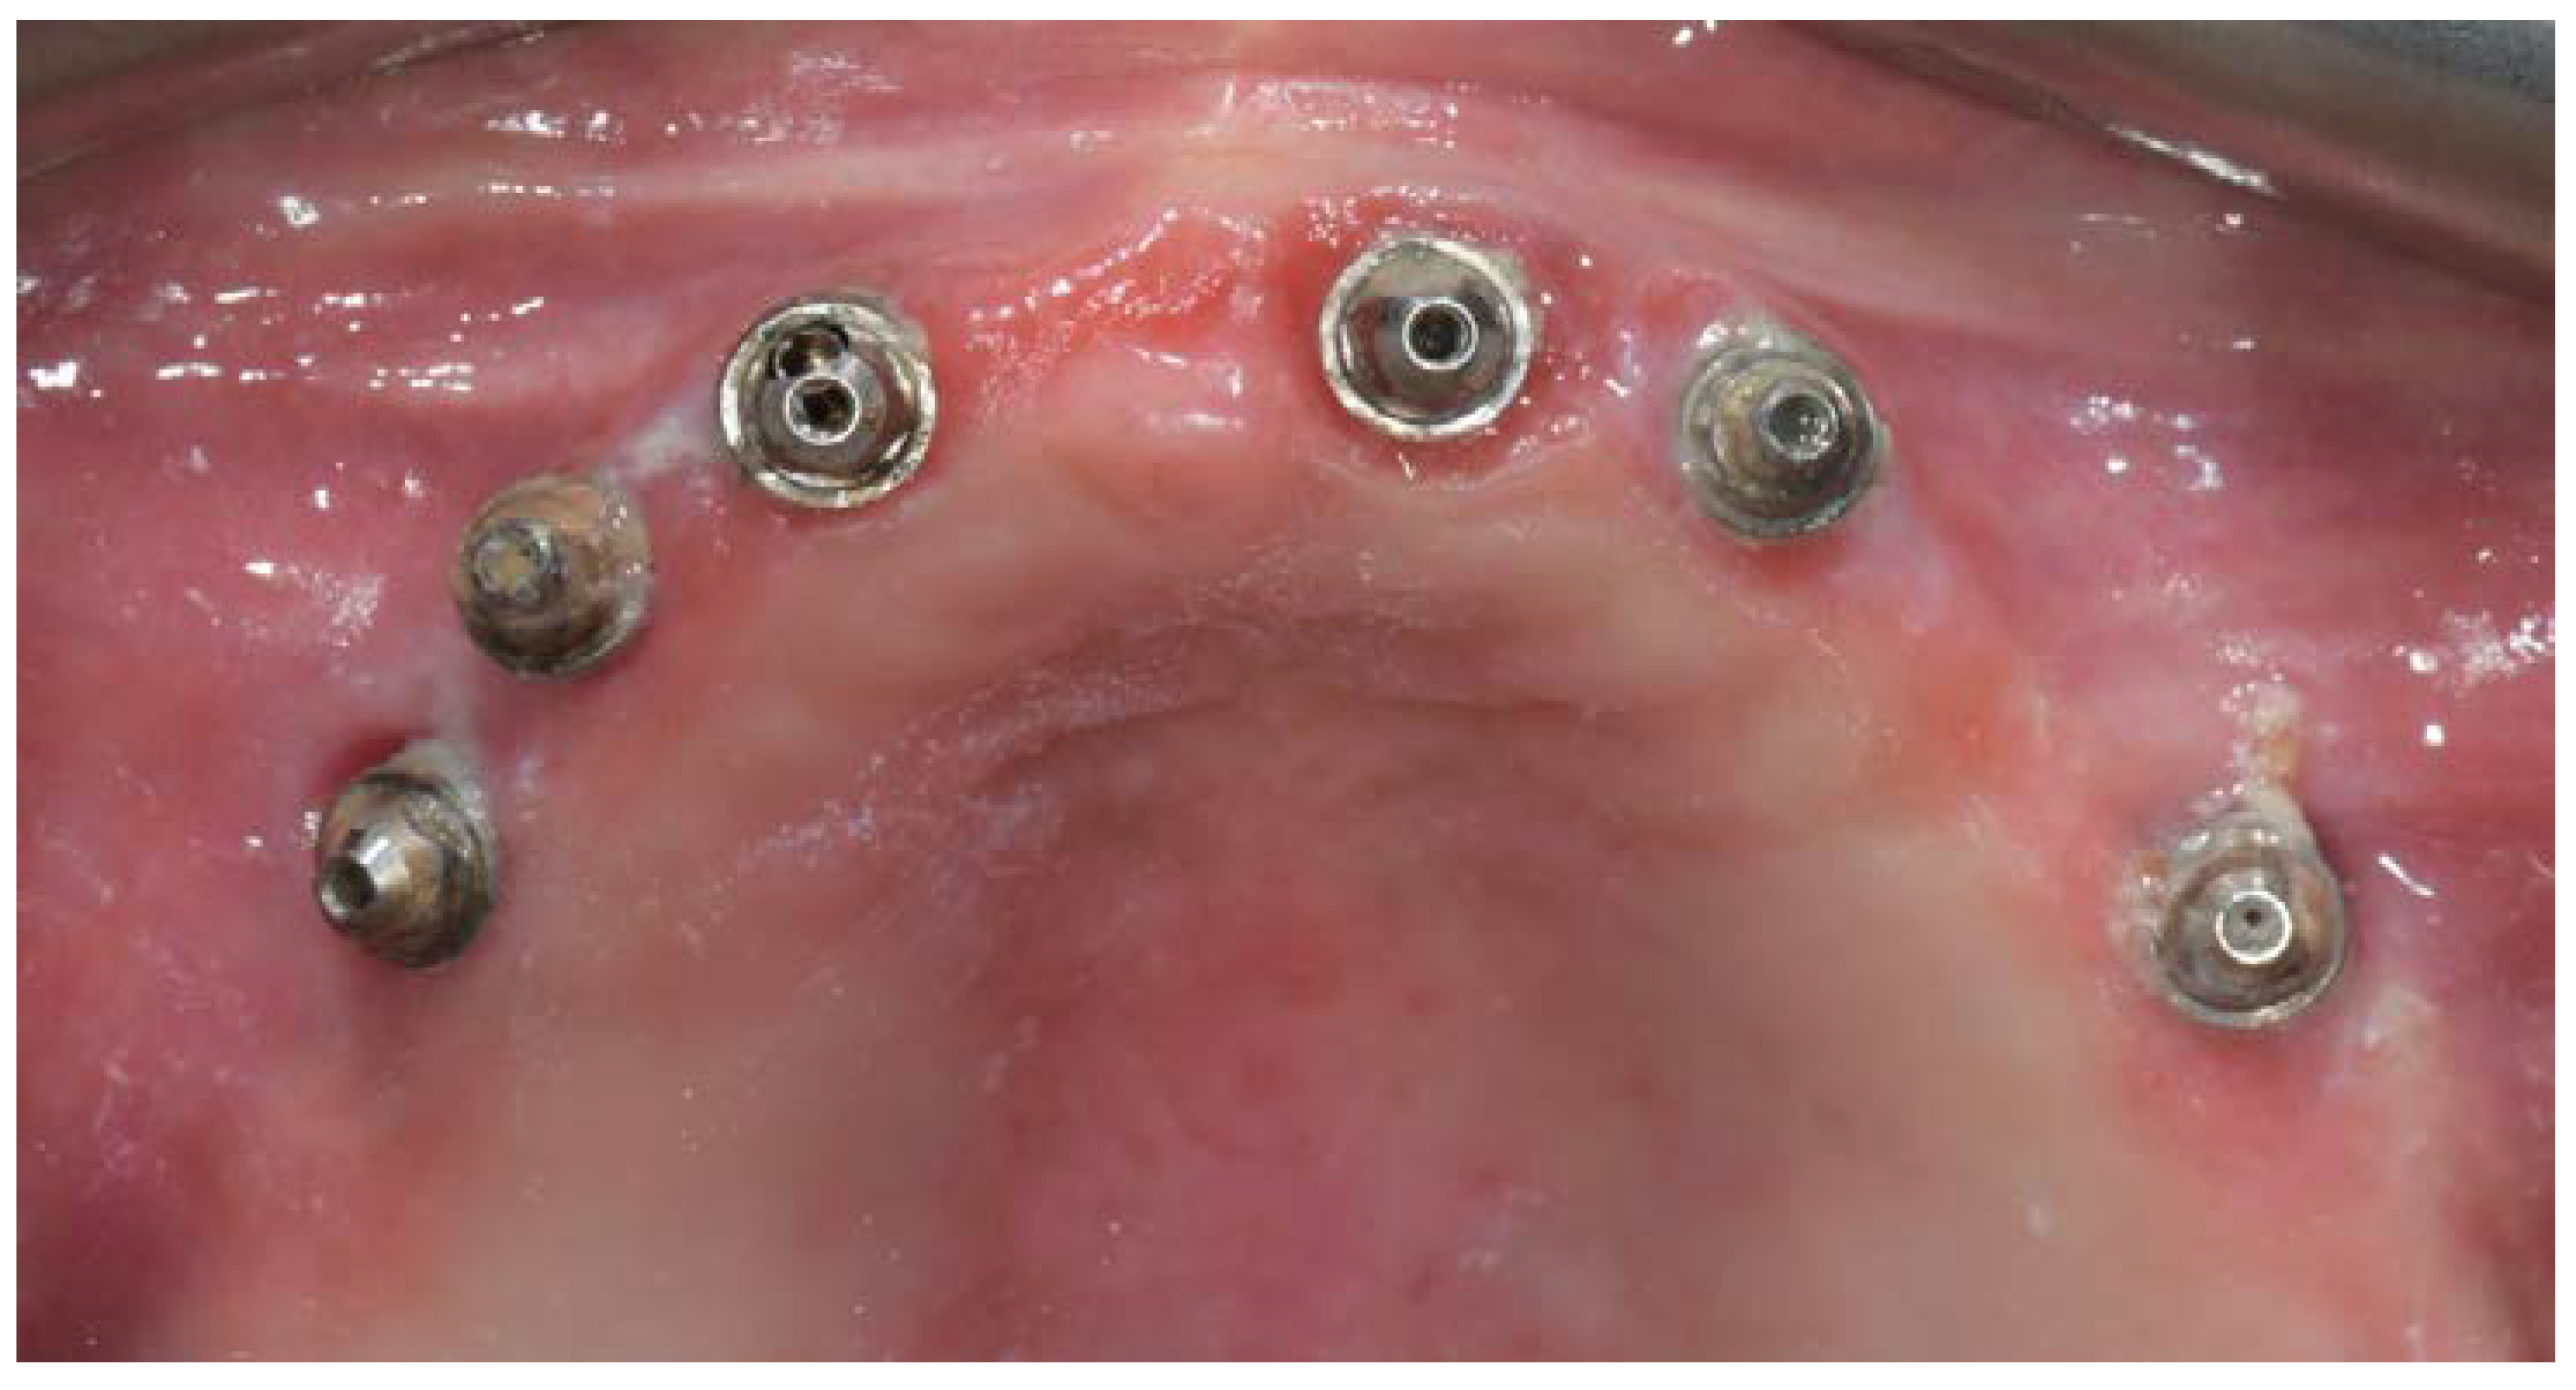

A partially edentulous 78-year-old woman with a complete screw-retained implant-support hybrid prosthesis (Figure 1) in the upper jaw and natural dentition in the lower jaw was referred to a private center in Rome, Italy, due to several continuous breakages of the prosthetic part of the implant-supported rehabilitation. After a preliminary interview, the patient stated that the implant treatment was finished two years before, but she had never been comfortable with this prosthesis (Figure 2). Relevant symptoms were phonetic difficulties, inability to maintain hygiene, and repeated breakages, leading to functional and esthetic issues (Figure 3). After that, the patient’s medical history was collected, and preoperative photographs, radiographs, periodontal screening results, and model casts were obtained for initial evaluation (Figure 4). During the clinical examination, the actual prosthesis was unscrewed, due to teeth detachments, and replaced with the old temporary prosthesis delivered by the patient. Both existing prostheses were evaluated and judged inaccurate, with particular attention to the fit of the prosthesis, the vertical dimension of occlusion, phonetics, facial support, and lip position. All the possible treatment options were then discussed and evaluated together with the patient. The main concerns of maintaining the previously placed implants were some exposed threads and the troubling disparallelism that makes the prosthetic treatment difficult, increasing the risk for biological complications and technical complications, respectively (Figure 5). Nevertheless, the patient refused a complete removable denture, so that implant removal would lead to placement of new implants, in combination with guided bone reconstruction and soft tissue management. This treatment plan may have the risks of implant failure and increased patient morbidity (Table 1 and Table 2). An implant-supported fixed dental prosthesis was initially excluded due to the implant’s disparallelism. Hence, a maxillary implant-supported overdenture was initially considered quite possibly the best therapeutic option.

Figure 5.

Intraoral picture of the implant positions and the multi-unit abutment screwed on.